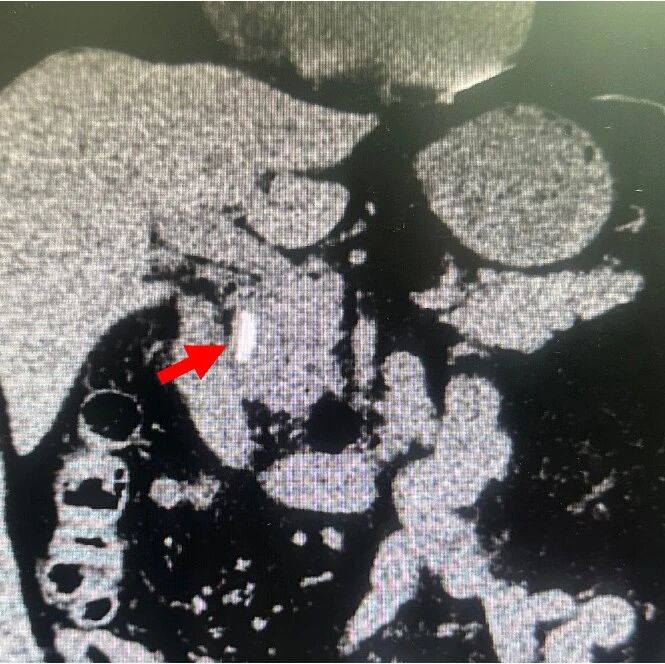

有多种术中成像技术用于提高腹腔镜胆囊切除术的安全性,包括术中胆管造影(IOC)、吲哚菁绿(ICG)荧光成像(FI)和腹腔镜超声(LUS)。本文主要探讨了良性胆道疾病腹腔镜胆囊切除术的最佳术中成像技术。 展开